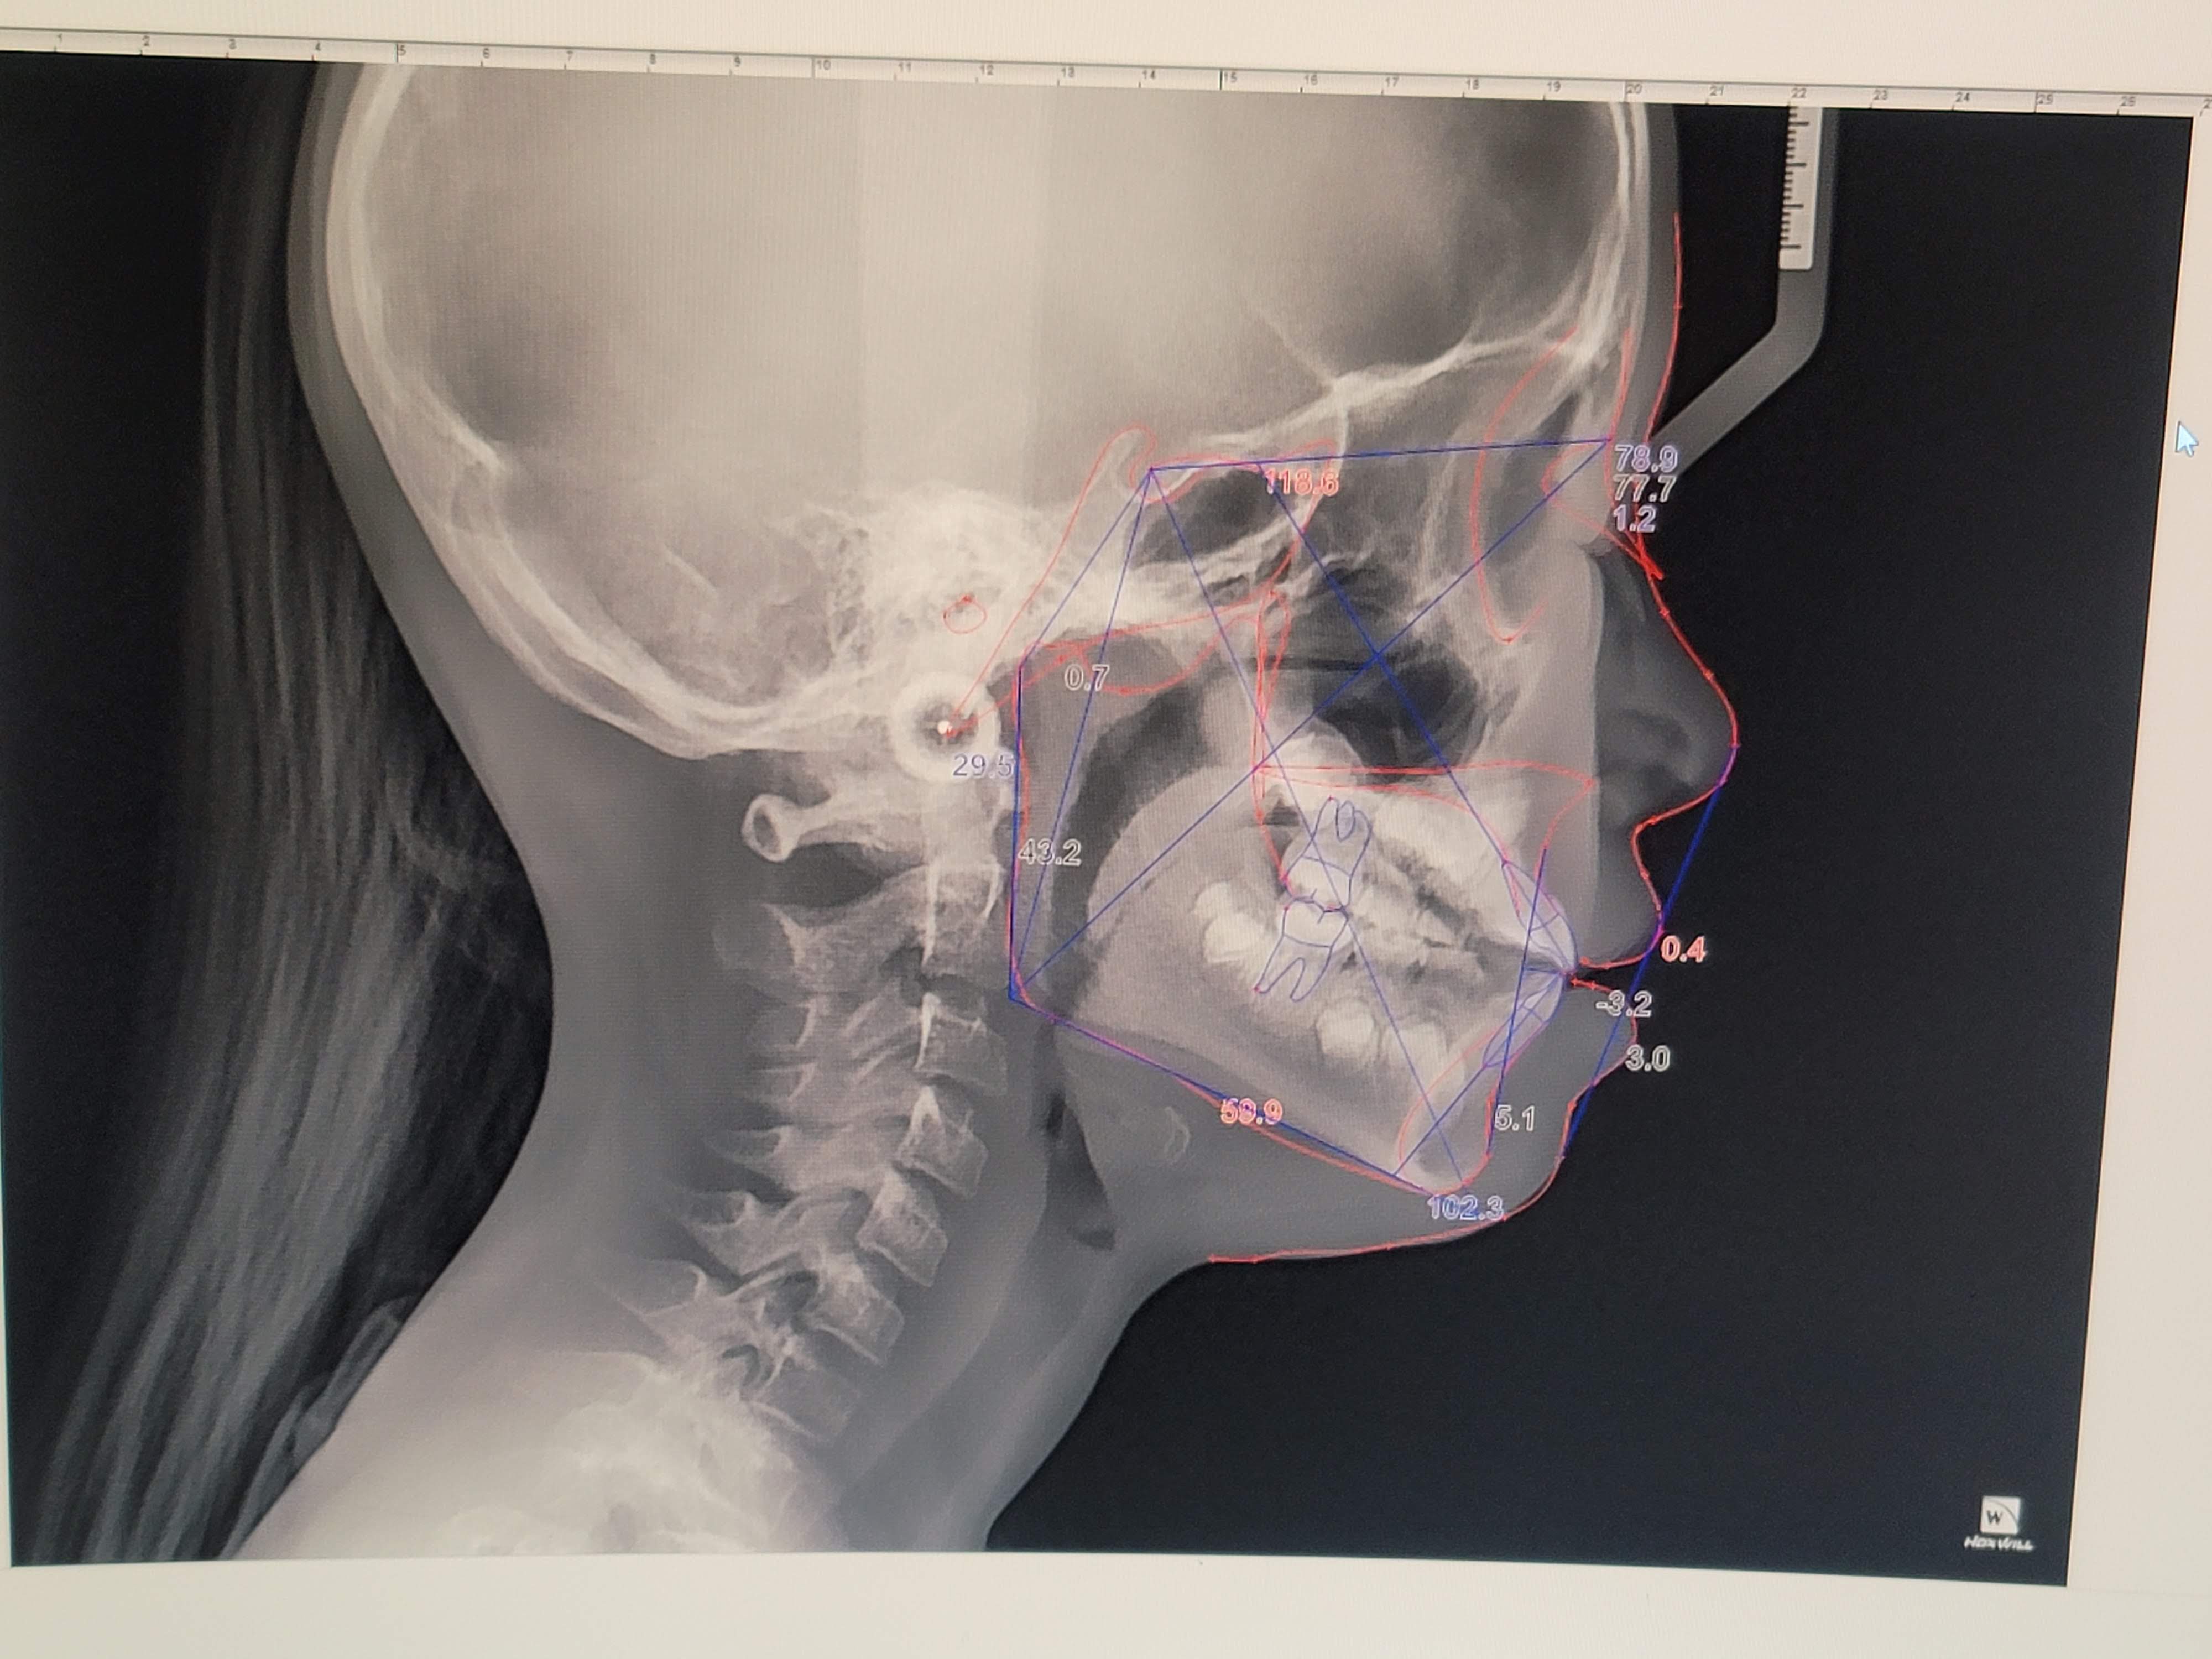

상담에 앞서서 엑스레이 촬영과 몇 가지 검사를 하였습니다.

그리고는 치아와 골격 구조를 검토해서 적절한 치아 교정법을 추천해 주셨습니다.

우리아이는 아래턱이 약간 튀어나와서 윗니와 부딪히는 구조입니다.

윗니가 아랫니와 부딪치고, 윗니와 아랫니가 서로 자라는데 방해를 하고 있습니다.

자라면서 윗니는 앞으로 점점 기울어지는 뻐드렁니 형태가 될 가능성이 높다고 하네요.

그래서 아랫턱을 뒤로 미는 교정법을 추천하셨고, 1차 교정을 진행하기로 결정했습니다.